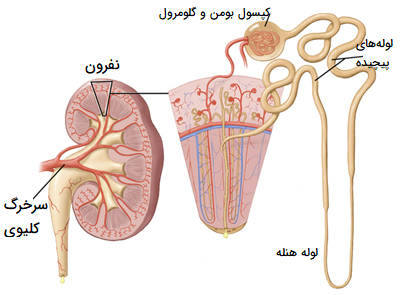

عکس کلیه در بدن. اگر پشت یا پهلوی شما آسیب ببیند مثل برخورد ضربه ممکن است فکر کنید که کلیه هایتان درد می کنند. مقدار و نسبت ترکیب این اخلاط در بدن هر شخصی و در اندامهای. کلیه گ رده ها1 از اندام های درونی بدن انسان به صورت یک جفت عضو لوبیایی شکل در طرفین ستون فقرات روی جدار پشتی شکم و بیرون از حفره صفاق قرار دارند. ک لیه ق لوه میز یا گ رده یکی از اندام های درونی بدن انسان و برخی دیگر از جانداران است.

در هر ساعت کلیه های بدن انسان حدود ۷ لیتر مایع را از خون جدا می کنند این مایع را تصفیه کرده و مواد مفید و سودمند آن را به خون بازمی گردانند و مواد مضر آن را از راه میزنای به مثانه می فرستد تا دفع شوند. کجای بدنتان درد می کند مراجعه کنید آیا کلیه تان درد می کند درد کلیه در اثر عفونت کلیه یا آسیب رسیدن به آن ایجاد می شود. اما کار و وظیفه کلیه ها در بدن چیست بیا یاد بگیریم. زمانیکه کلیه ها بدرستی فعالیت کنند مواد زائد از بدن داخل ادرار ترشح می شوند همچنین کلیه ها در تنظیم سایر مواد معدنی در بدن مانند.

کلسیم و فسفر که برای تشکلی استخوان لازمند کمک می کنند مواد. کلیه ها با تولید ادارد در دفع مواد زاید تعادل الکترولیتی تنظیم هورمونی تنظیم فشار خون و هوموستازگلوکز نقش دارند. آناتومی کلیه انسان در بدن انسان به این شکل است که کلیه ها دو عضو لوبیایی شکل در دستگاه ادراری بوده و به دفع مواد زائد به صورت ادرار کمک می کنند. یکی از مهم ترین وظایفی که کلیه ها در بدن بر عهده دارند پاک کردن و تصفیه خون از زباله هاست.